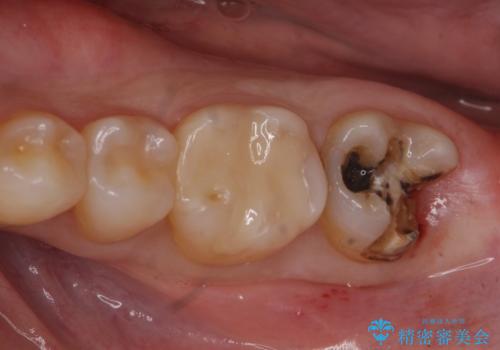

- 銀の詰め物が取れたとのことで来院。

詰め物の下には虫歯がありました。

白い物で治療して欲しいとのことで、セラミックの詰め物だと詰め物の範囲が大きく、割れてしまう可能性があるので

ジルコニアクラウン(被せもの)で治療を行いました。

銀の詰め物はかなり昔に治療されたそうです。

銀の詰め物は虫歯の再発リスクが高く、歯に痛みが出てしまうと歯の神経の治療もしないとならなくなってしまいます。